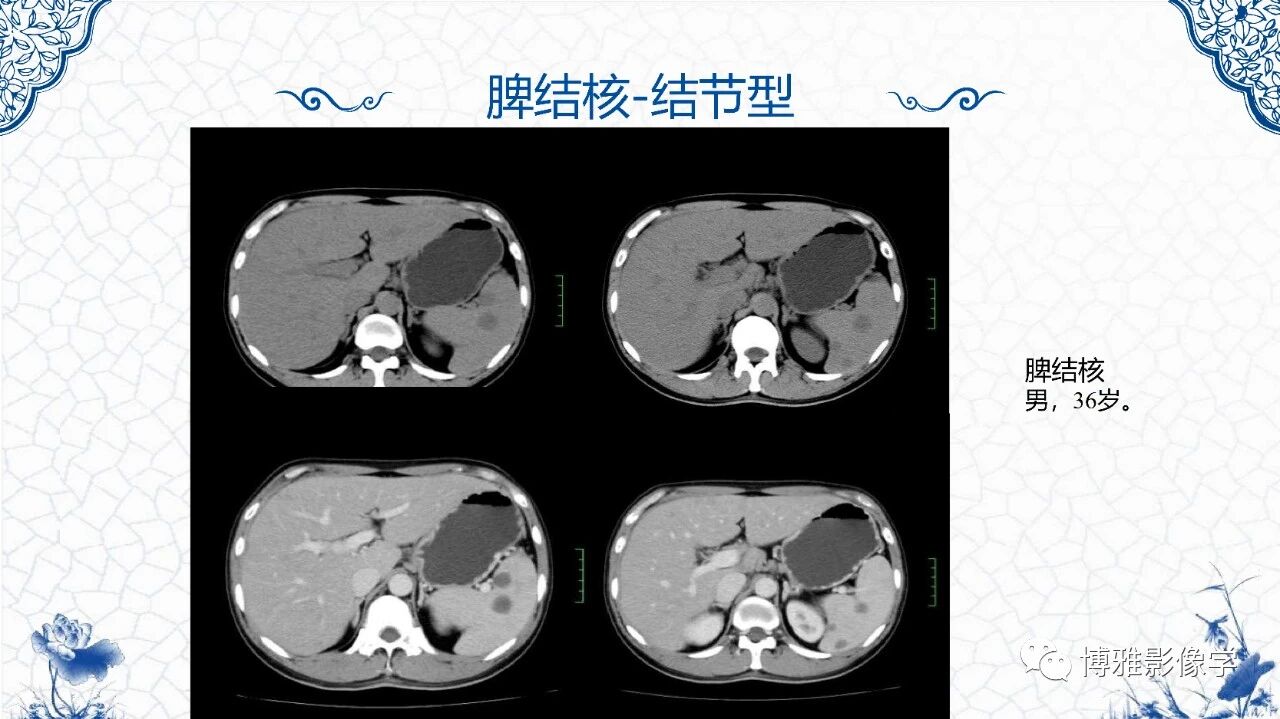

[腹盆] 脾脏非肿瘤影像诊断

脾脏非肿瘤影像诊断